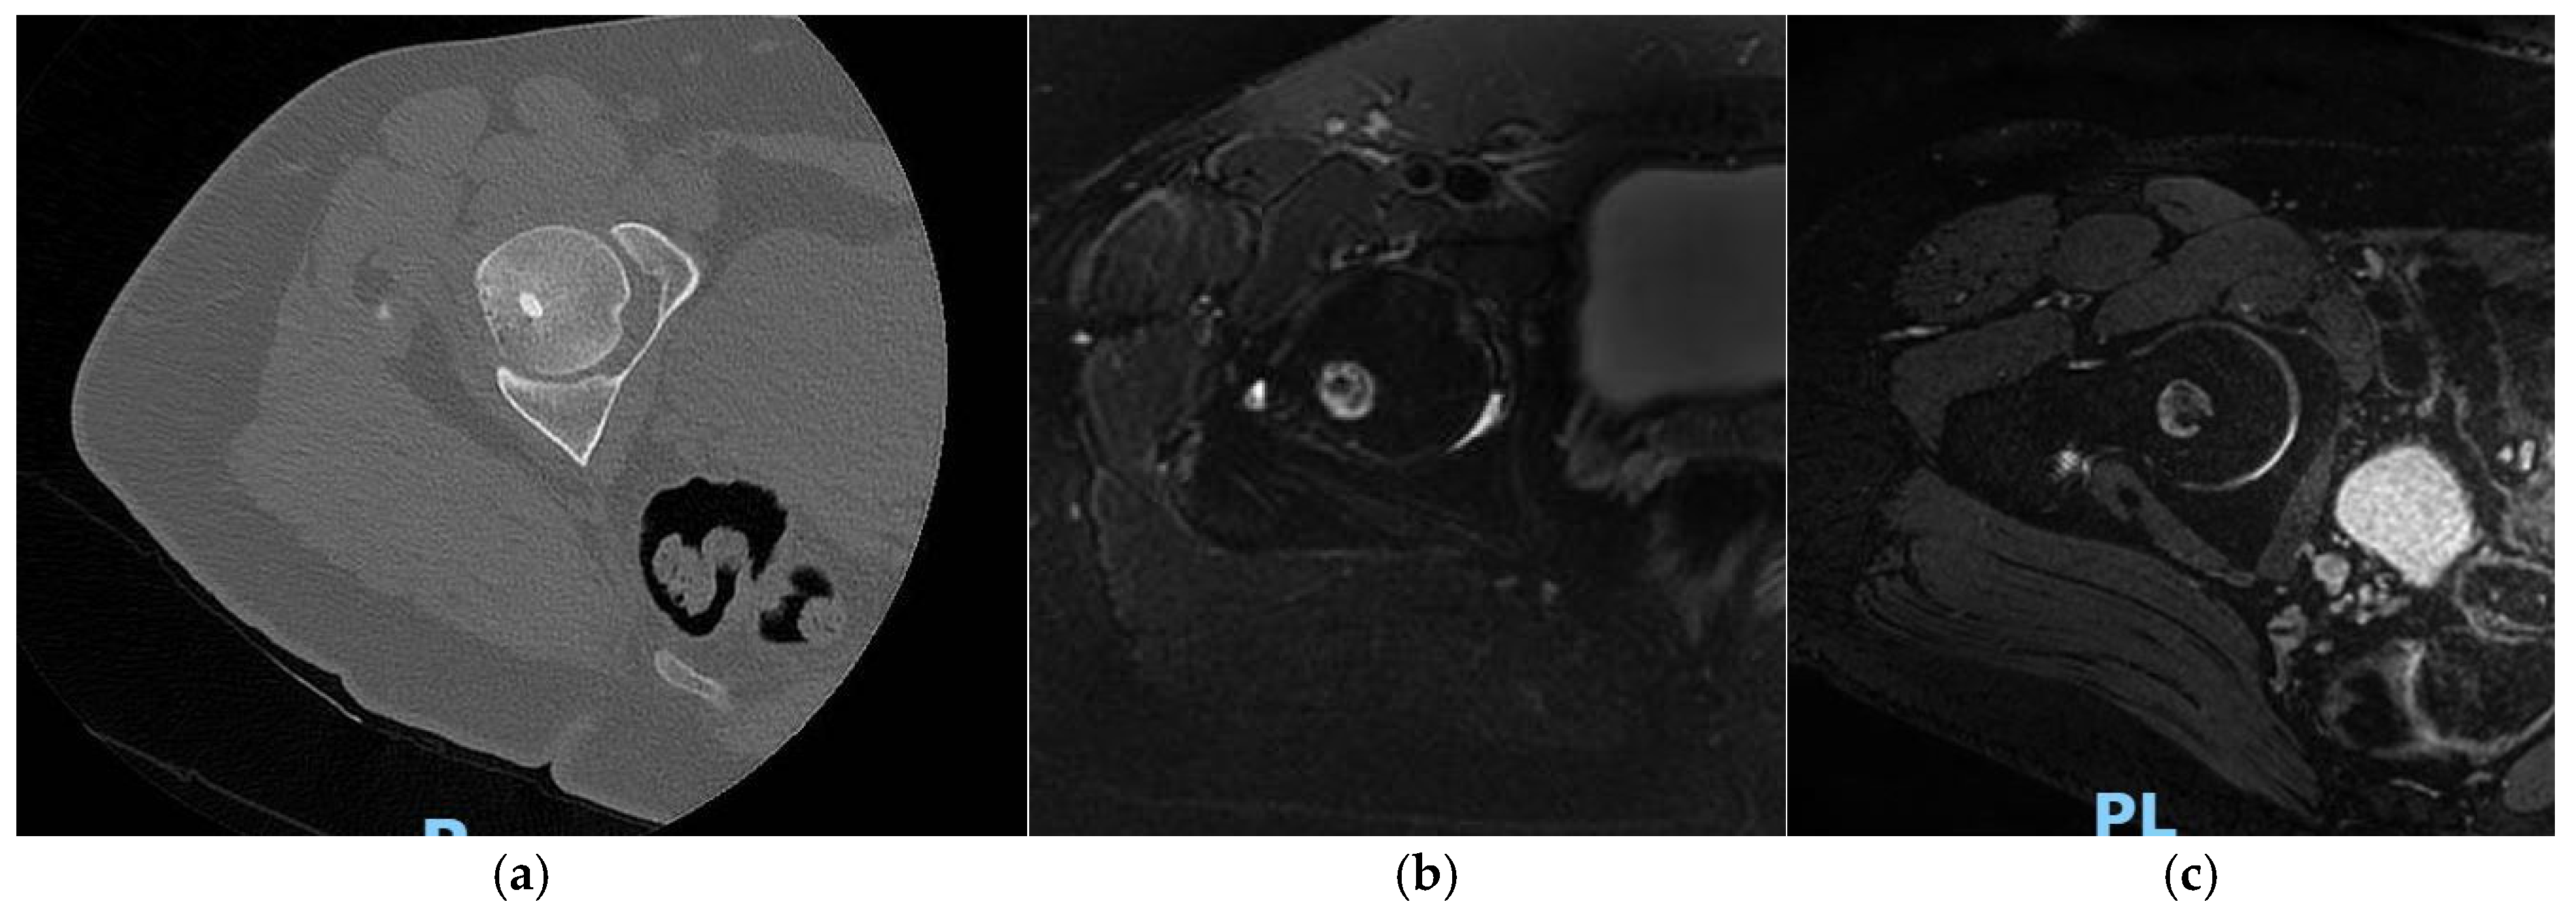

The aim of their study was to define the main findings on the imaging that can best describe the regular evolution of these types of treatments. Four findings were considered by the authors as particularly relevant (Figure 1): (1) bone marrow edema; (2) reactive phenomena (perilesional inflammatory reaction for extra-articular lesions or synovial reaction for intra-articular ones); (3) bone remodelling (disappearance of the nidus and bone healing); (4) ring sign (granulation tissue around the treated nidus). These findings were assessed using MRI and CT with a follow-up study that lasted up to 24 months. Thirty-four patients were evaluated; during the follow-up period, the authors noticed a consistent reduction of all inflammatory signs such as, for example, the bone marrow edema, which was significantly reduced. Furthermore, synovitis disappeared in 53% of patients and was reduced in the other 46%; the perilesional inflammatory reaction was significantly reduced in 76% of the patients and disappeared in 24% [27].

Figure 1.

Osteoid osteoma of the femoral head: CT (a) and MRI T2W image with fat saturation (b): perilesional reaction without marrow bone edema; (c) after 6 months, the lesion is dimensionally stable.

After one month from the treatment, the site of the nidus is usually replaced by cicatricial/fibrotic tissue [28]. Progressively, MRI follow-up exams show a reduction of the perilesional bone marrow edema. Contrast-enhanced MRI is important in the diagnosis of OO, since enhancement of the nidus is a pathognomonic sign. MRI is also a crucial tool in the early identification of possible post-treatment disease relapses [29,30]. Some studies support this last suggestion, for example Mahnken et al. studied 20 patients and demonstrated that contrast enhancement on T1-weighted MRI imaging seems to be predictive of treatment failure after radiofrequency ablation for treatment of OO [30]. MRI is also useful to assess post-procedural complications, for example adjacent soft tissues lesions or osteomyelitis [31]. The results of percutaneous RFA for treatment of OO, as reported in the literature studies, are summarized in the Table 1.